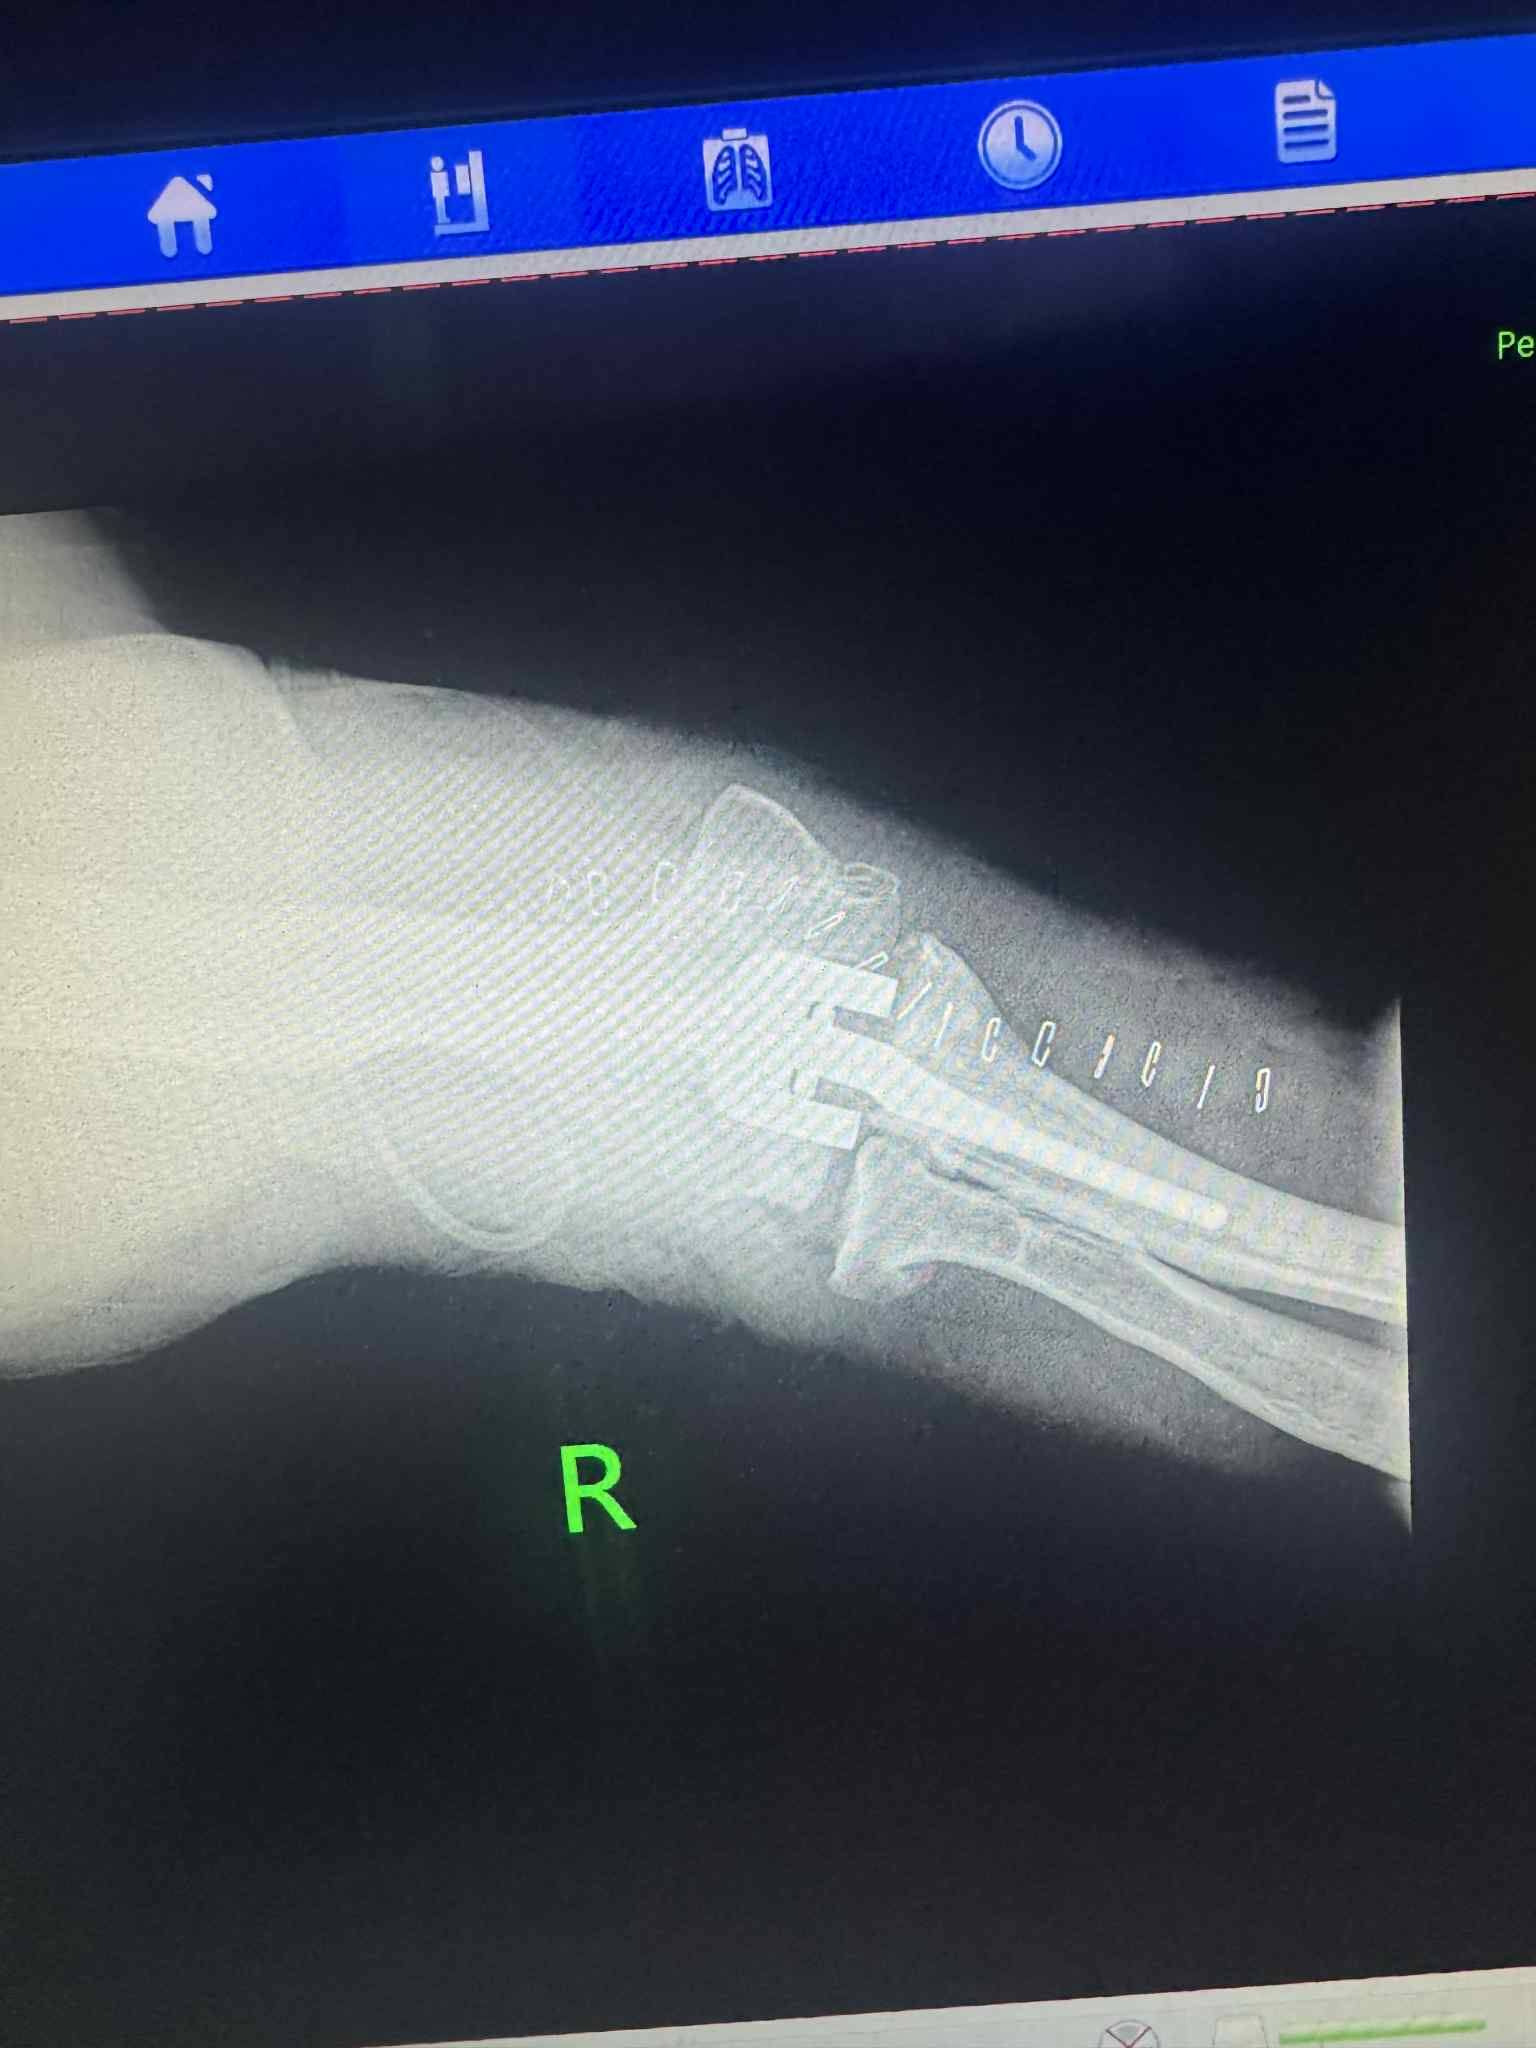

Төв аймгийн Нэгдсэн эмнэлгийн мэс заслын тасгийн гэмтлийн эмч нар Гэмтэл согог судлалын үндэсний төвийн эмч нартай хамтран орон нутагтаа анх удаа тохойн үе бүтэн солих мэс заслыг амжилттай нэвтрүүллээ.

Уг хагалгааны багийн бүрэлдэхүүнд: Гэмтэл согог судлалын үндэсний төвийн гар сарвууны мэс заслын тасгийн эрхлэгч Л.Нанжид, Гар сарвууны мэс заслын эмч Ж.Баярмагнай, Ц.Санжаасүрэн, Мөнгөн гөлтгөнө ХХК-ны үений мэс заслын эмч Э.Дөлгөөн болон аймгийн Нэгдсэн эмнэлгийн гэмтлийн эмч З.Мөнхчулуун, Г.Гантулга, Ц.Жамъянгарав, Мэдээгүйжүүлгийн эмч Г.Бат-Оргил, мэс заслын сувилагч Ө.Ширнэн, мэдээгүйжүүлгийн сувилагч Жаргалцэцэг, туслах сувилагч Р.Нямдолгор нар оролцлоо.